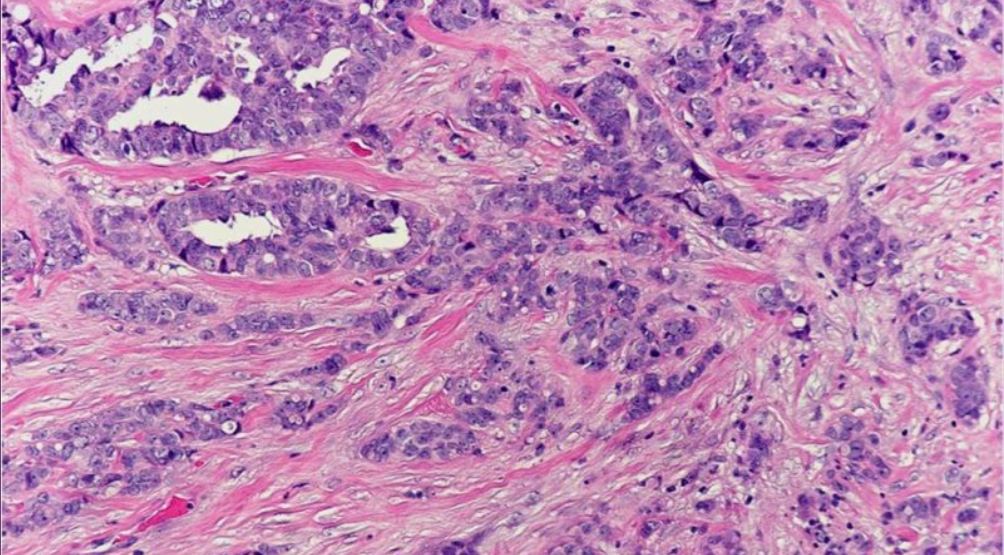

The classification problem tackled here is to classify histopathology slides of Invasive Ductal Carcinoma (IDC) as either malignant or benign.

IDC is a type of breast cancer, where the cancer has spread to the surrounding breast tissue.

Cancer tumours can be classified into two types: malignant and benign. A benign tumor is one which does not invade its surrounding tissues whereas a malignant tumor is one which may spread to its surrounding tissues or other parts of the body.